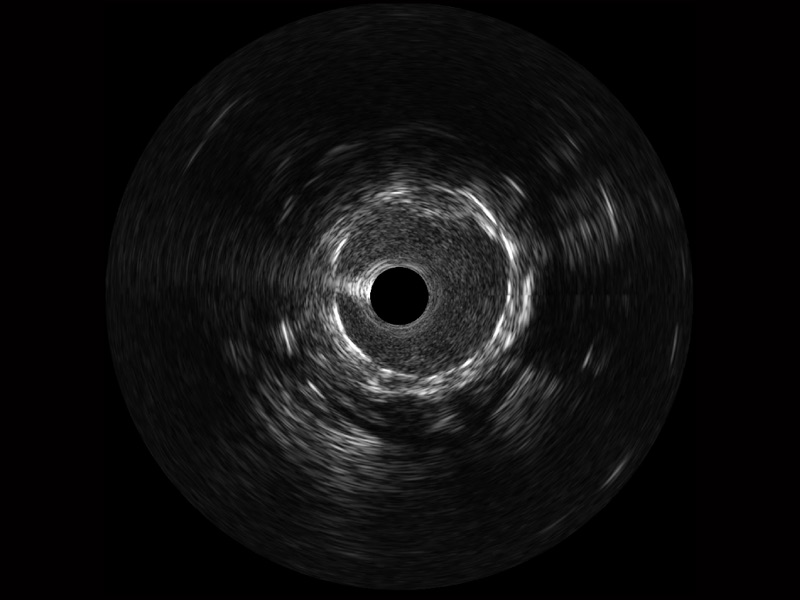

传统IVUS图像

对比传统IVUS导管成像,DB中国旗舰官方网站宽频IVUS图像的近场支架梁显影更细腻,远场中膜外血管仍清晰可辨,兼顾远中近,兼顾分辨力与穿透深度